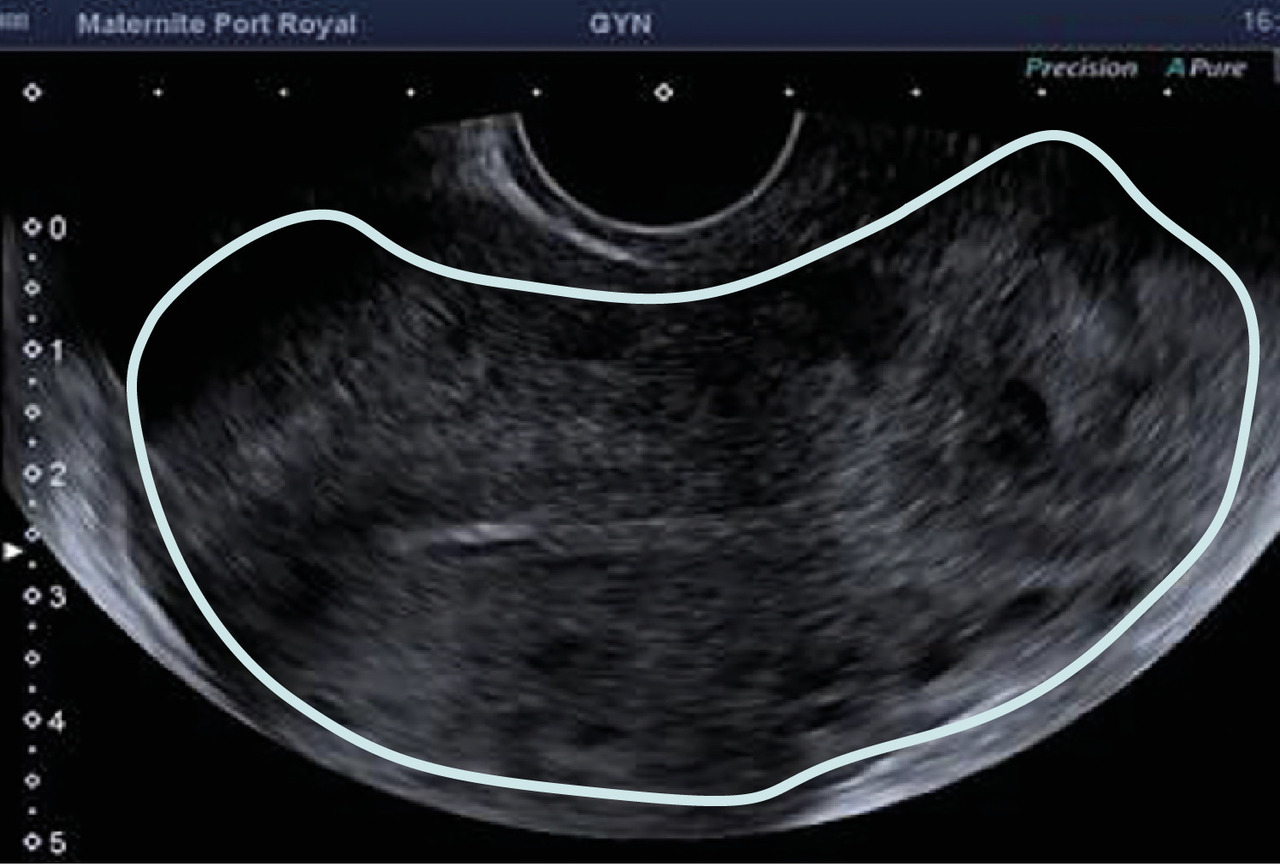

L’échographie, indispensable, doit examiner le pelvis mais aussi l’abdomen. Elle est donc réalisée par voie endovaginale, sus-pubienne et abdominale. On peut visualiser une masse latéro-utérine (fig. 1). Au sein de cet hématosalpinx, un sac gestationnel peut être visible, voire un embryon (fig. 2) ayant parfois une activité cardiaque positive. Le passage de la sonde à ce niveau est douloureux.

– vacuité utérine (fig. 3) et taux de hCG supérieur à 1 500 UI/L, fortement évocateurs. En cas de métrorragies, une lame d’hématométrie peut être visible en intra-utérin (« pseudo-sac gestationnel » : image hypo-échogène centrée dans la cavité, sans couronne trophoblastique) ;